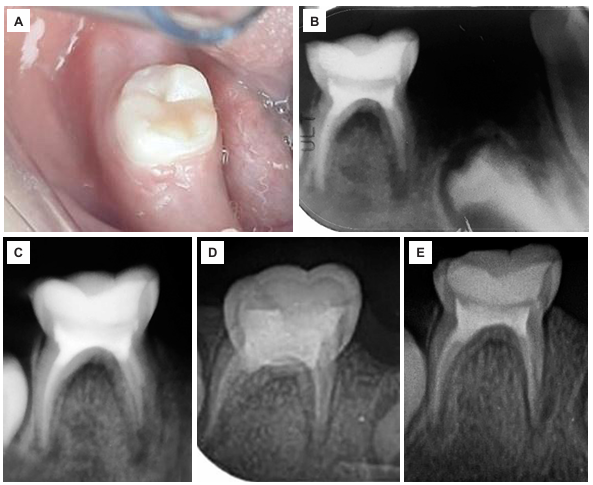

Una semana después, se realizó el primer control, en el cual la madre manifestó que la niña ya no presentaba dolor y podía masticar mejor sus alimentos. En la evaluación clínica, se evidenció que los tejidos circundantes no presentaban alteraciones y la restauración se encontraba con un sellado marginal óptimo (figura 3A). Radiográficamente, se observó una imagen radiopaca compatible con la restauración coronaria, el sellado cameral y la obturación de los conductos radiculares, junto con un proceso osteolítico interradicular y periapical, acompañado de osteítis condensante circundante (figura 3B).

En el segundo control, realizado 15 días después del tratamiento, la niña se mostró más sociable con el personal odontológico, y la madre reportó ausencia de molestias tras el procedimiento. El examen clínico de la pieza 85 reveló tejidos gingivales sanos, sin dolor a la percusión, y la restauración en buen estado. Radiográficamente, se evidenció un adecuado sellado de la restauración coronal y de los conductos radiculares; sin embargo, se identificó una imagen radiolúcida a nivel interradicular y periapical, con alteración en el patrón óseo trabecular circundante, lo que sugiere la presencia de un área en proceso reparativo (figura 3C).

Figura 3 Control clínico y radiográfico de la pieza 85 a través del tiempo. A) Primer control clínico a la semana del tratamiento. B) Primer control radiográfico a la semana: radiografía periapical. C) Segundo control radiográfico a los 15 días. D) Tercer control radiográfico a los 20 días. E) Cuarto control radiográfico a los 2 meses.

En el tercer control, 20 días después del tratamiento, la niña ingresó tranquila y mostró una actitud colaboradora durante el examen odontológico. Clínicamente, los tejidos blandos y duros circundantes a la pieza 85 se encontraban en buen estado, mientras que la evaluación radiográfica reveló una restauración coronaria oclusal adecuada, sellado cameral correcto y obturación completa de los conductos radiculares; sin embargo, se identificó una secuela de la reabsorción radicular externa en la raíz mesial (figura 3D).

Dos meses después, en el cuarto control, la paciente mantuvo una conducta receptiva durante la evaluación. Clínicamente, la pieza 85 presentaba la restauración en buen estado, sin signos de molestias. Radiográficamente, se observó un buen sellado de la restauración oclusal y de los conductos radiculares, además de una reducción de la imagen radiolúcida en la zona interradicular, lo que sugiere un proceso de recuperación en marcha (figura 3E).